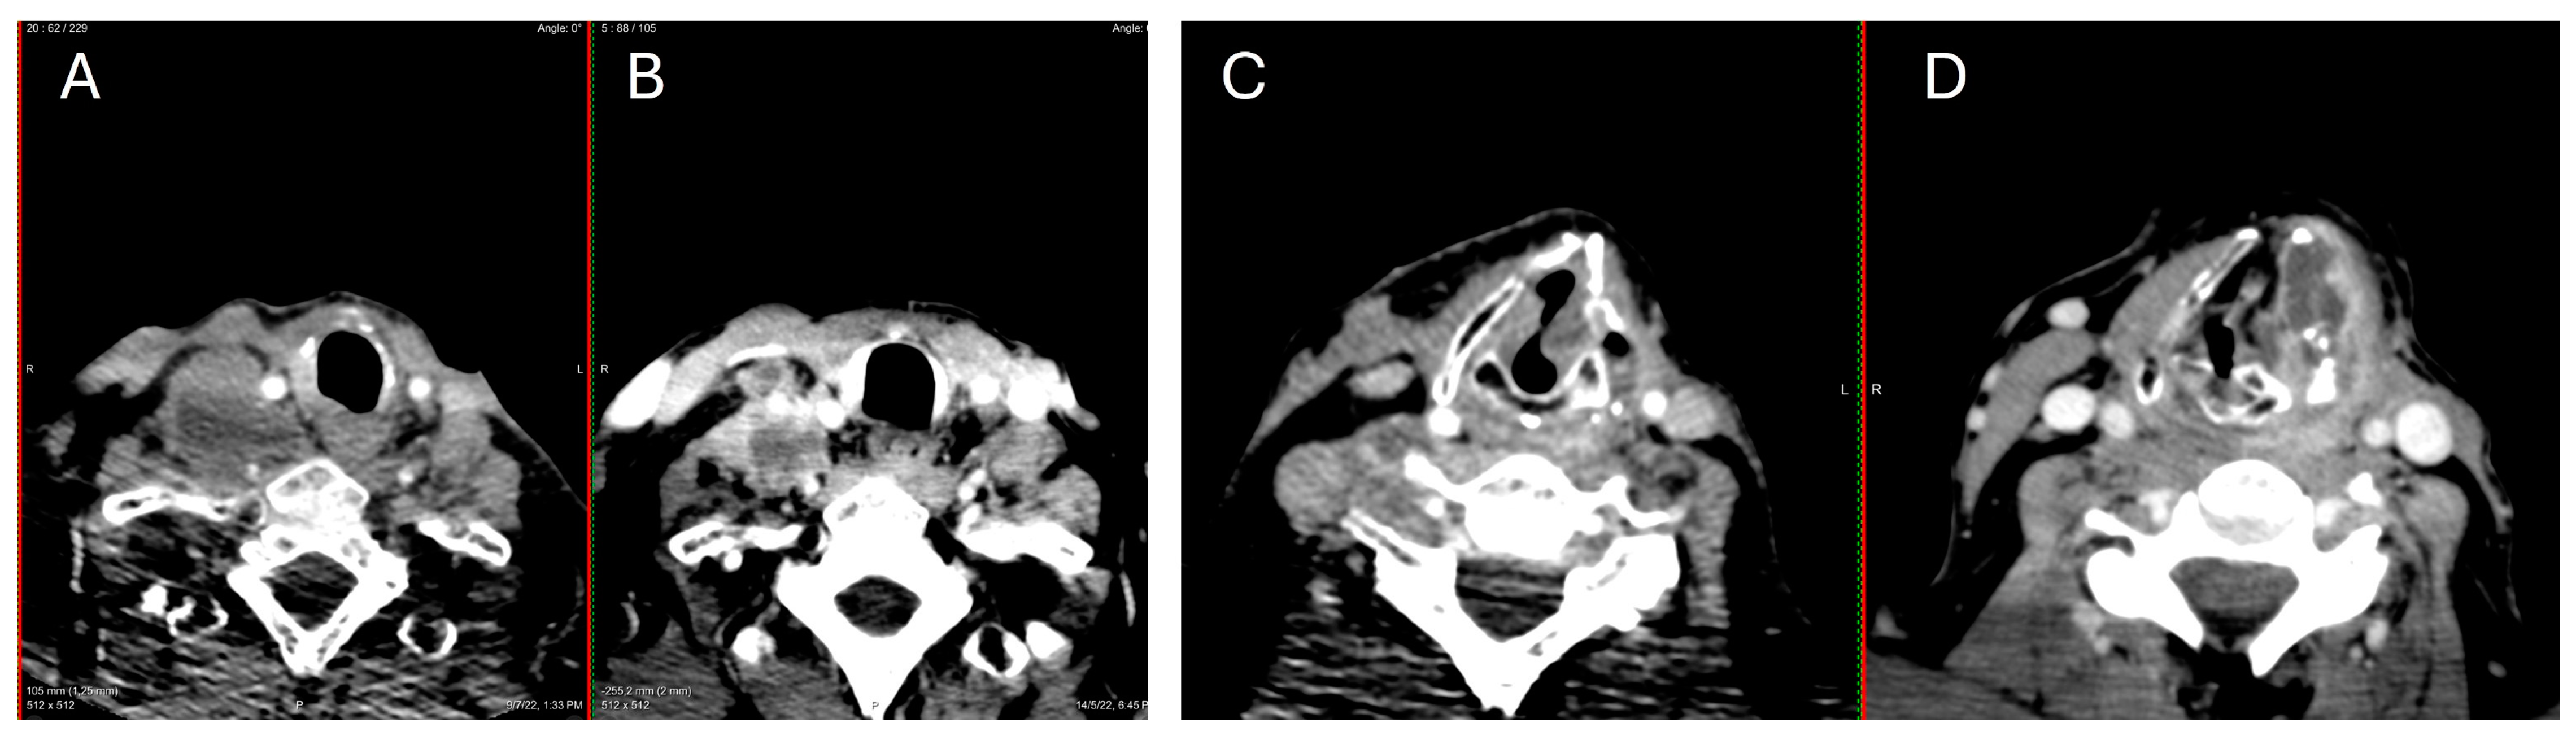

| PRESENT CASE | 1 | 1/0 | 45 | PDTC, hobnail, tall-cell | 1/1 | 1/1 (brain, bone, sinus) | 1/1 | TTmy (+neck dissection, completion ND) | 2 | Lenvatinib, sorafenib, trametinib/dabrafenib | DOD | BRAF |